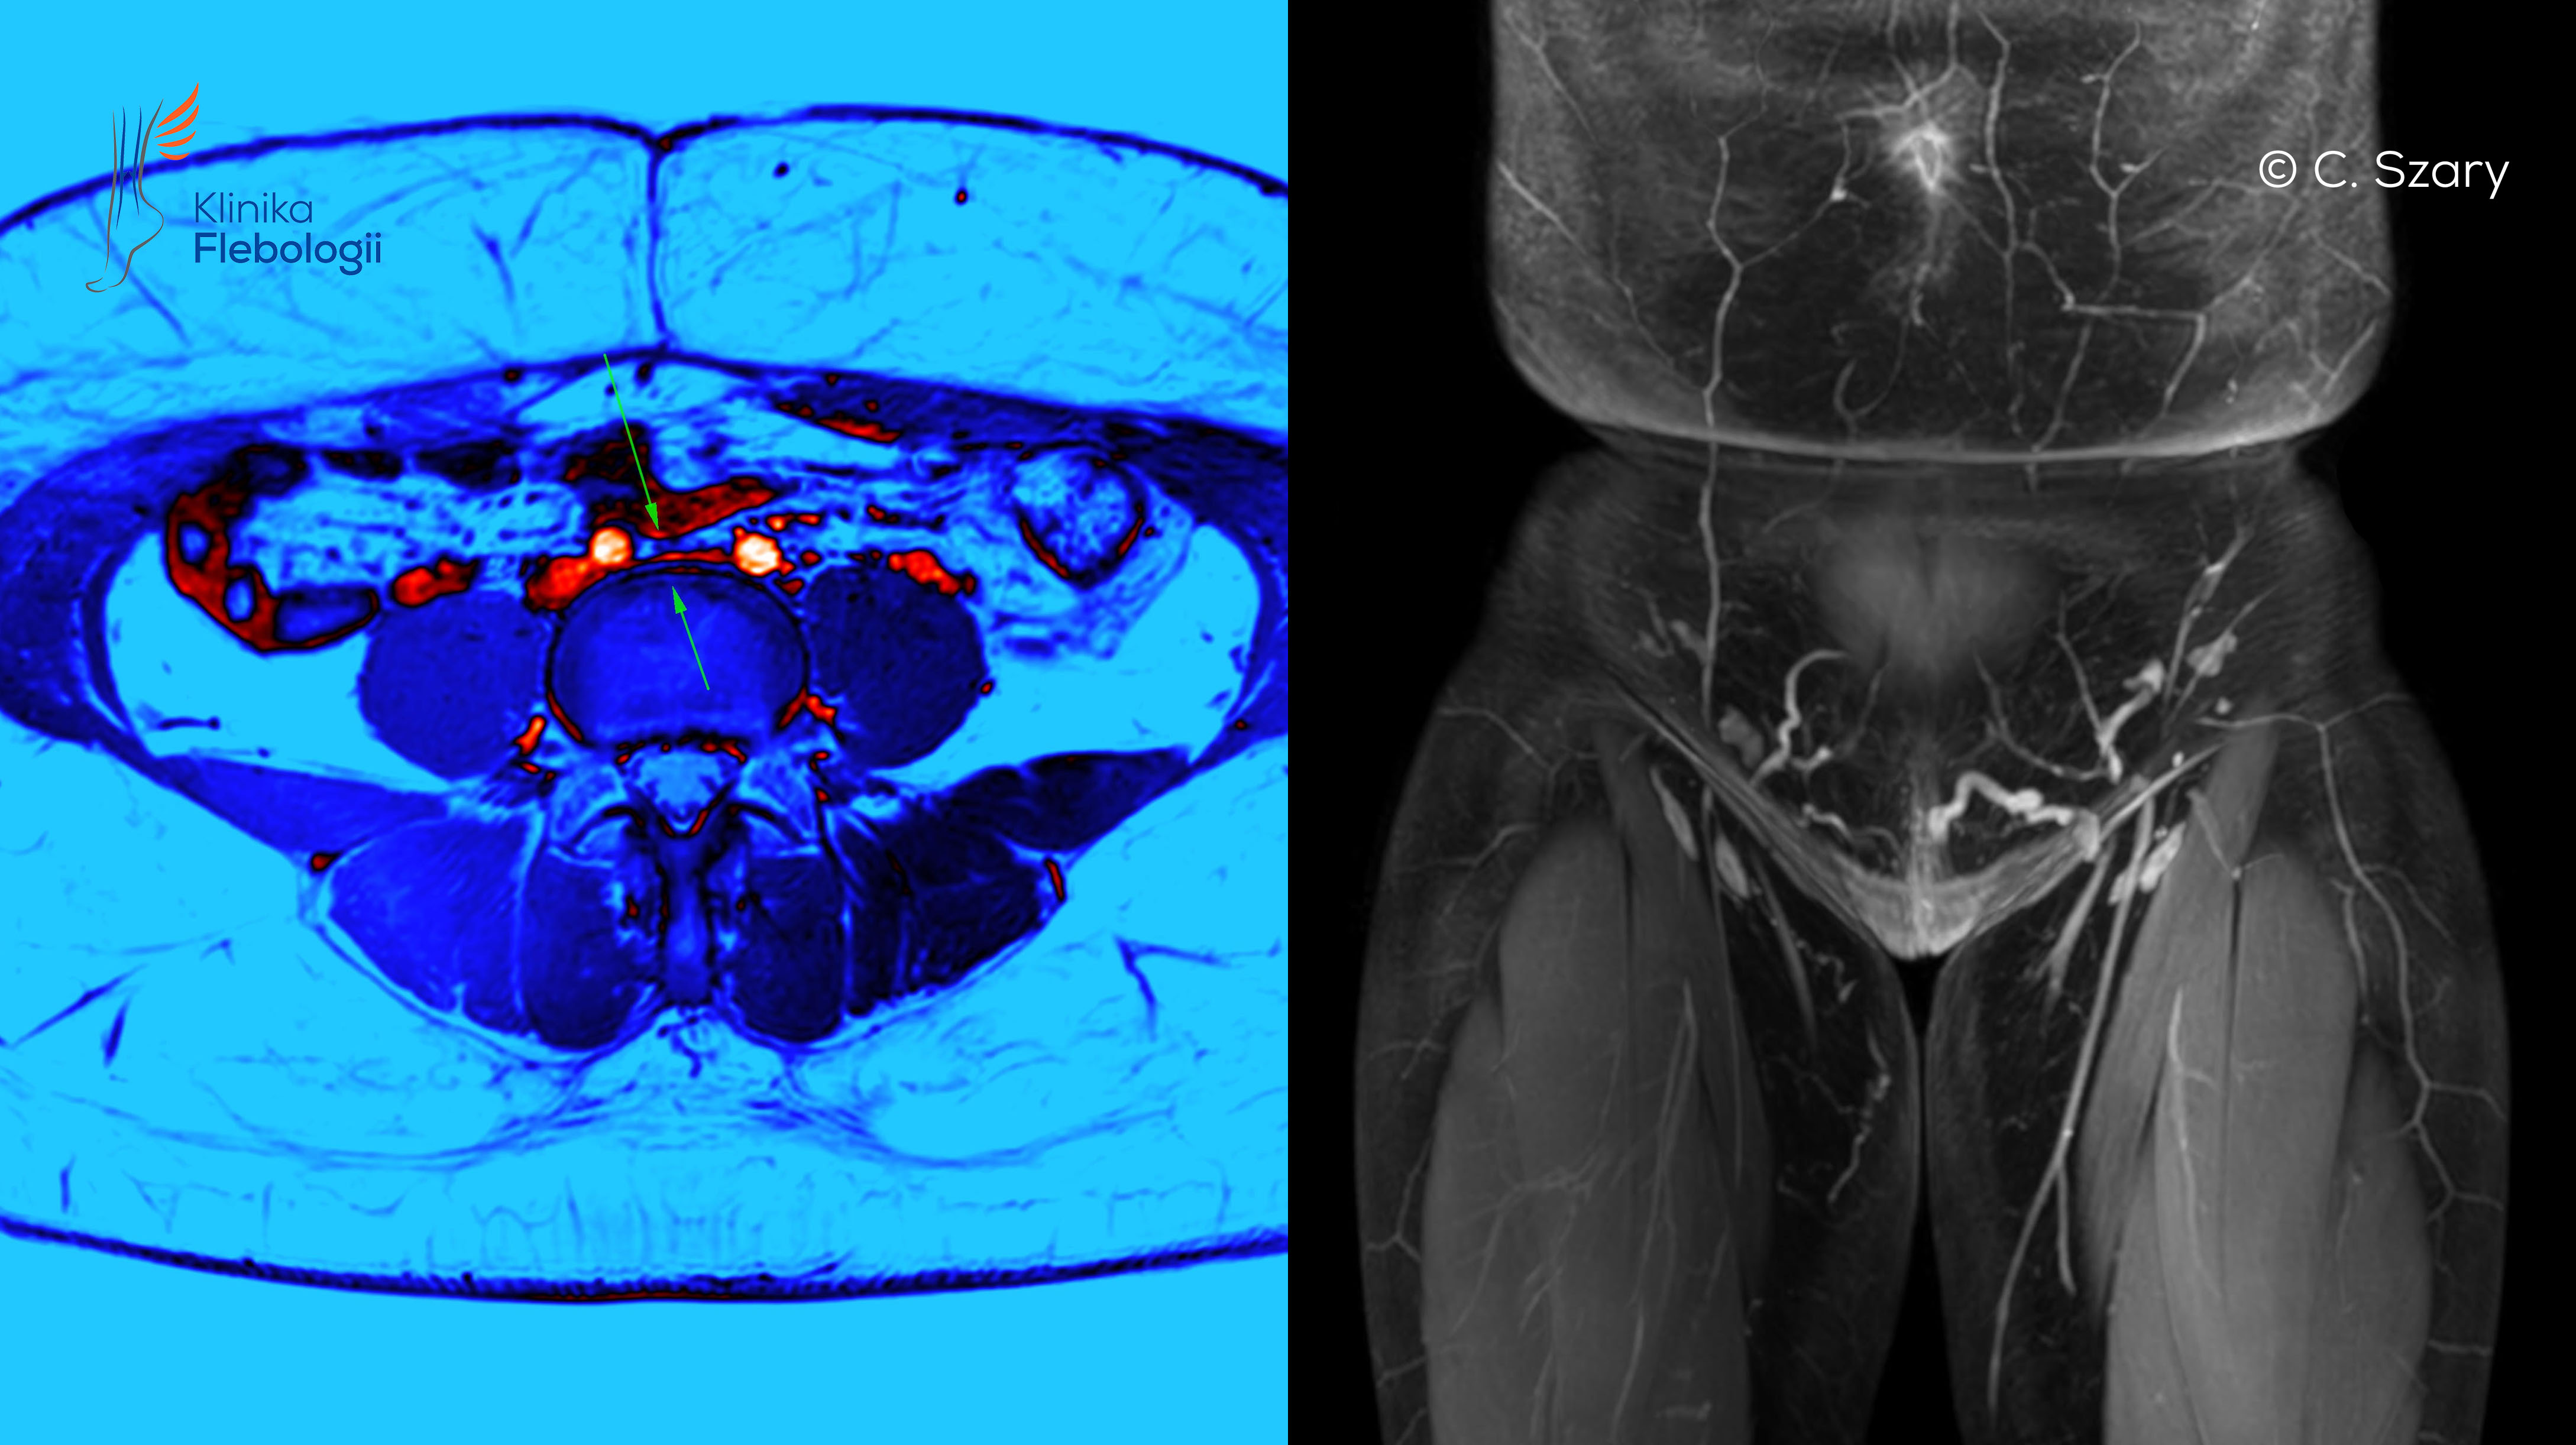

Zespół May-Thurnera związany jest ze zjawiskiem zaburzonego odpływu krwi żylnej z obszaru spływu układu żył biodrowych po lewej stronie ciała. Do ucisku dochodzi typowo na poziomie skrzyżowania tętnicy biodrowej wspólnej prawej z żyłą biodrową wspólną lewą. Ujawnianie się tego typu nieprawidłowości anatomicznych występuje częściej u kobiet. W wielu przypadkach pewne objawy skrzyżowania naczyń widoczne są już przed porodem, a w sposób najbardziej dobitny po urodzeniu pierwszego dziecka

Ucisk lewej żyły biodrowej wspólnej na poziomie jej skrzyżowania z prawą tętnicą biodrową wspólną i niekorzystne konsekwencje z tego wynikającego, to jedno z ważniejszych zjawisk anatomicznych w układzie żylnym, doprowadzające do wczesnej niewydolności żylnej miednicy, niewydolności żylnej kończyn dolnych (częściej lewej), a także groźnej dla życia zakrzepicy proksymalnej w lewej kończynie dolnej.

Zjawisko May-Thurnera ujawnia się najczęściej u kobiet będących w ciąży. Wynika to bezpośrednio ze zwiększającej się ciasnoty w czasie wzrastania płodu i dodatkowych niesprzyjających warunków w odpływie krwi żylnej z miednicy.

Diagnostyka żylnych zespołów uciskowych oparta jest współcześnie na wykorzystaniu najnowszych metod obrazowych. Często należyte zdiagnozowanie problemu i zaplanowanie leczenia wymaga użyciu kilku z poniższych metod. W dalszym ciągu badaniem z wyboru, szczególnie na etapie wstępnym, jest dobrze wykonane badanie USG Doppler żył kończyn dolnych, okolic intymnych, miednicy małej i jamy brzusznej.

W zależności od potrzeb diagnostycznych specjaliści Kliniki Flebologii wykonują pełne spektrum badań obrazowych układu żylnego, tj.: